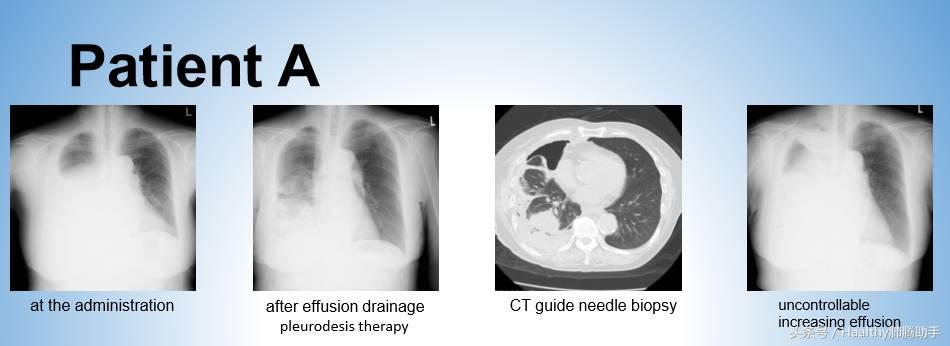

患者A 女性 77岁

患者A的胸腔积液中并无发现癌细胞,因此先行胸膜固定术,控制胸腔积液,并接受CT引导的穿刺活检以进行病理检查和基因检测。

患者A需要等待24天才能获得病理、基因检测结果,等待期间她接受了20天最佳支持治疗。

检查结果显示患者A病理是肺腺癌,没有EGFR突变和ALK融合 ,由于疾病进展,患者A于初诊25天后接受培美曲塞+卡铂化疗。

然而由于癌细胞快速扩散,胸腔积液无法控制,患者A于第一周期化疗开始后58天死亡。